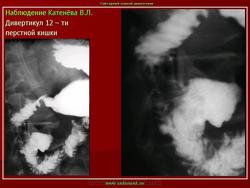

Дивертикулы 12-ти перстной кишки.

Дуоденальный дивертикул